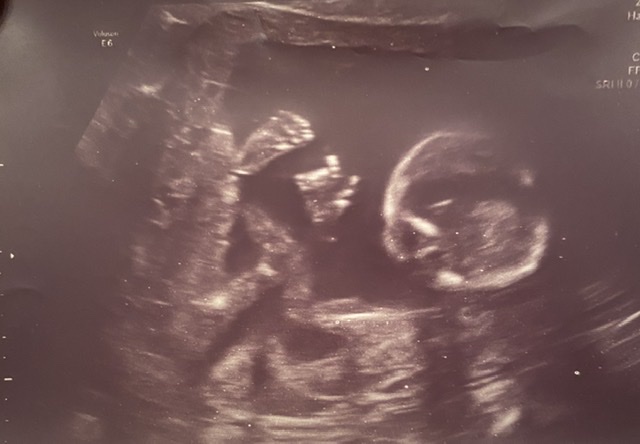

УЗИ 16+2 и фото

Вышли мы в полном восторге. Изначально мы мечтали о девочке, но на первом скрининге мне предположили мальчика. Конечно же мы все-равно были рады этой новости, стали придумывать имя, но вчера нас шокировали известием о девочке❤️Врач дала 95% 😁 Малышка соответствует сроку, продемонстрировала все свои пальчики, весит 150г))) Врач обрадовала тем, что плацента поднялась на 2 см ( на первом скрининге она перекрывала зев), шейка 40 мм. ТТТ все хорошо.

И в дополнение фото малышки и коллаж моего ещё небольшого живота. Мама вообще говорит, что я его на втором фото выпучила. Но мы то с мужем знаем , что это не так) Растёт пузяка медленно, но верно. К вечеру то вообще на все 6 месяцев.